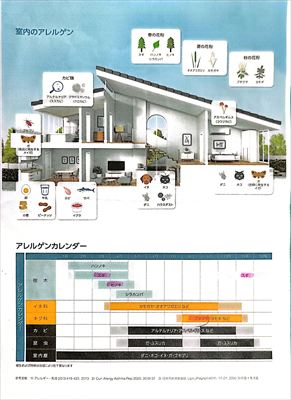

採血によりアレルギー検査(大きな8項目)